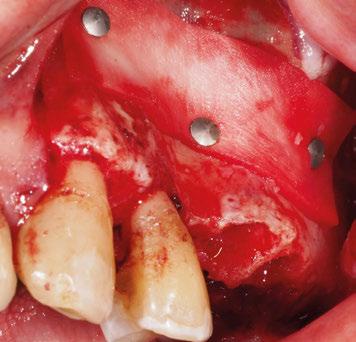

maxilectomía parcial que incluyó las piezas 24-26 y desde el reborde alveolar hasta la base del cráneo (Figuras 3 y 4). En este caso, la órbita y el globo ocular pudieron ser preservados. La reconstrucción inmediata se realizó mediante un colgajo de músculo temporal homolateral (Figura 5) y el defecto de la fosa temporal fue cubierto mediante una malla de titanio. Posteriormente, la paciente recibió radioterapia (Figuras 6 y 7). 2 años más tarde se diseñó un IS con anclaje en el arbotante nasomaxilar, zona subnasal izquierda

y lo que se pudo preservar del hueso malar. Se añadió una malla sinterizada infraorbitaria para dar volumen a la mejilla y se planificaron dos brazos de conexión que emergieran en las posiciones 24 y 26 de forma subgingival (Figuras 8 y 9). La superficie interna que apoyaba en el hueso era de titanio microrrugoso, y la superficie externa y conectores de titanio pulido y hexágono externo universal (Figuras 10 y 11). La cirugía se hizo bajo anestesia general en infiltración con anestesia local (4% articaína, 1:100.00 epinefrina), levantando el

colgajo cutáneo de la mejilla por vía intraoral, preservando el colgajo temporal para no comunicar con el remanente de la cavidad naso maxilar (Figura 12). Se emplearon 10 tornillos de osteosíntesis de 1,9 mm y la estabilidad primaria obtenida fue excelente (Figura 13)

8. Imagen 3D de la extirpación y planificación del implante subperióstico.

Posición de los tornillos de osteosíntesis y emergencia de las conexiones.

Figura

Figura 9.